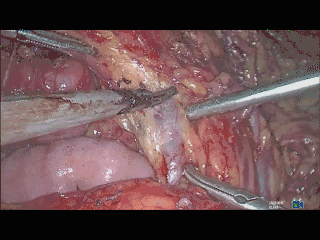

在管道的表面,沿管道长轴,刮过管道表面,将管道前方的组织轻轻刮开,吸走,显露目标管道及其走行。在刮的过程中,使用力量需恰当,能做到与管道表面接触而不压迫管道,用力太重易损伤管道,太轻则不能很好的显露目标。

挡血管,在淋巴结清扫暴露髂血管时,用吸引器挡静脉可替代分离钳的作用;

挡脏器,例如切除子宫缝合阴道残端时,用吸引器阻挡膀胱,协助主刀更好缝合阴道残端。下压阻挡肠管,协助暴露。向侧面压输尿管,使输尿管远离发烫的电器械,必要时给输尿管冲水,降低输尿管损伤风险。

通过吸引器头,使用适当的力量,顶在管道和周围组织之间,可以通过顶这个动作,将管道和周围组织间的间隙显露。当然,关键是找准位置,否则,再顶也不会出现间隙。